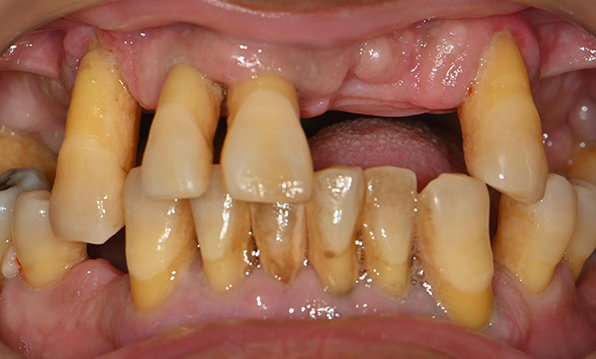

치아가 하나도 남아있지 않거나 전체적으로 상실된 경우 추천합니다.

전체 임플란트가 필요한 경우

치아가 얼마 남아있지 않은 경우

치주질환이 심해, 치아가 있더라도 제 기능을 하지 못하는 경우

틀니 사용이 불편한 경우